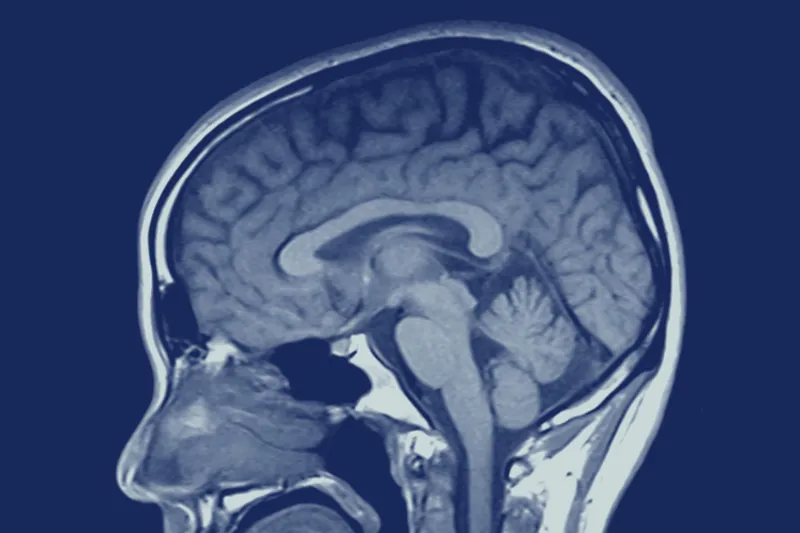

I den del af hjernen, der kaldes hippocampus – som spiller en nøglerolle ift. rumlig orientering og hukommelse – fandt forskerne efter 12 måneder øgede mængder af GFAP-positive astrocytter hos de tandløse mus. Disse celler betragtes som tegn på, at hjernen er blevet skadet, og øges i antal ved demenssygdom.

Derudover kunne forskerne konstatere, at proteinet Claudin-5 i samme del af de tandløse mus’ hjerner var reduceret radikalt.